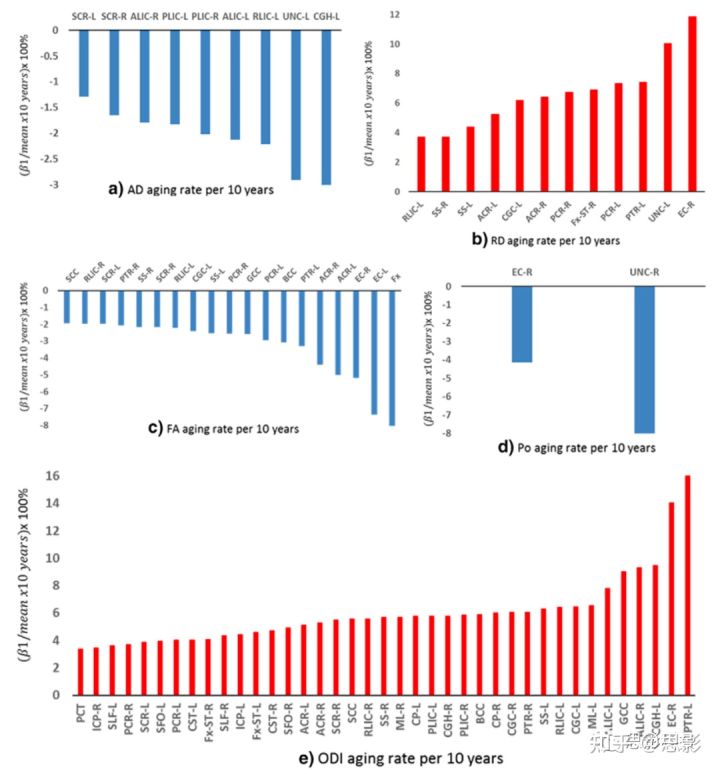

因为在回归模型1中,所有的扩散指标和ROI组合下β3都不显著,因此老化效应在两性中是一致的。因此,无论是回归模型2还是回归模型3的β1都被用来描述男女共同的老化效应。表3总结了白质ROI中那些显著的β1(斜率),图4显示了这些斜率每十年的变化百分比。图5为年龄相关的重要ROI中DTI和q空间分析的显著回归曲线。ODI的回归线如图6。DTI扩散指标随年龄变化的总体趋势是AD降低,RD增加,FA降低。MD在年龄上没有显著差异。同样,组织限制(P0)在大多数白质ROI中相对稳定,但在2个ROI中(包括钩状束,UNC)显著下降。与年龄相关的NODDI指标变化的总趋势是增加了纤维弥散度(ODI),其中显著的白质ROI发生率最高。轴突内体积分数(ICVF)稳定,所有白质ROI无显著变化。

图4 显著ROI中每十年扩散指标百分比变化的条形图。

使用表3中的β1除以表S3中所有受试者扩散指标的平均值,再乘以10年,计算每十年的变化百分比。

扩散指标中与年龄相关的定量变化

图4显示了各ROI的扩散指标的百分比变化。AD每10年下降1%-3%。在大多数ROI中,RD每10年增长3%-7.0%,但在右侧钩状束中,RD激增至12%。FA每十年下降1%-8%。P0下降了3%和8%。ODI增长了3%-16%。年龄相关的关键ROIs包括钩状束、穹窿和海马扣带回段,其变化率往往高于其他白质ROIs。